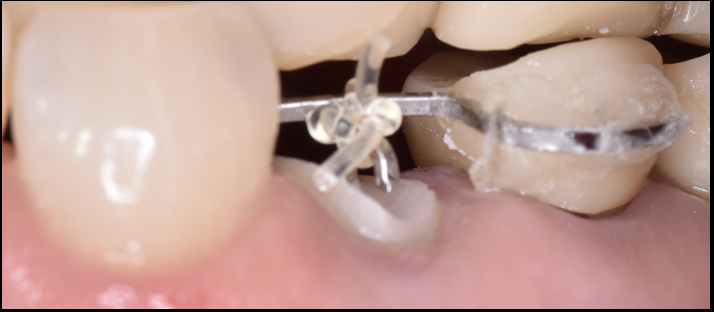

折れた歯を残す「エクストルージョン」という選択...